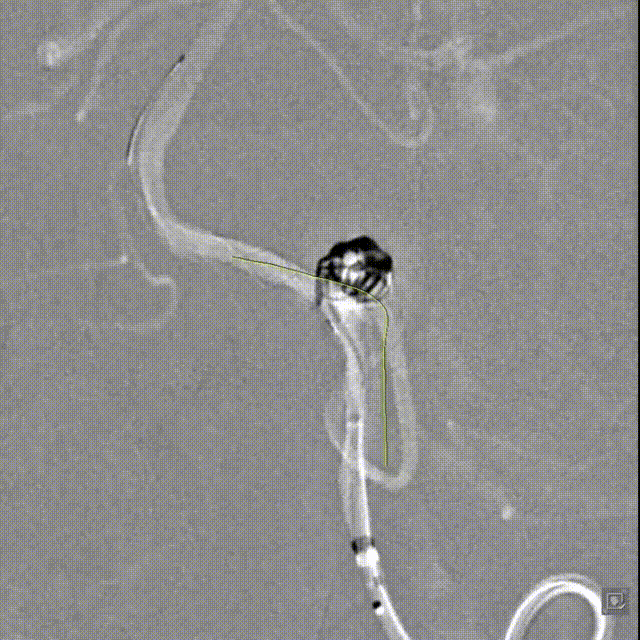

Tubridge Plus Case 2